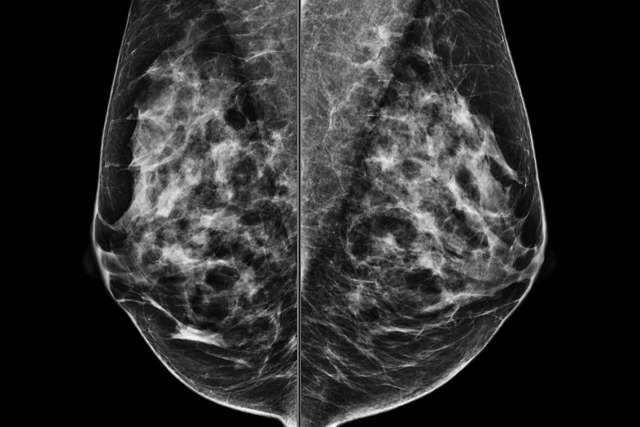

Screening Mammogram

Screening Mammogram (Screening vs. Diagnostic Mammogram)

How to obtain quality breast imaging from positioning to post-processing interpretation.